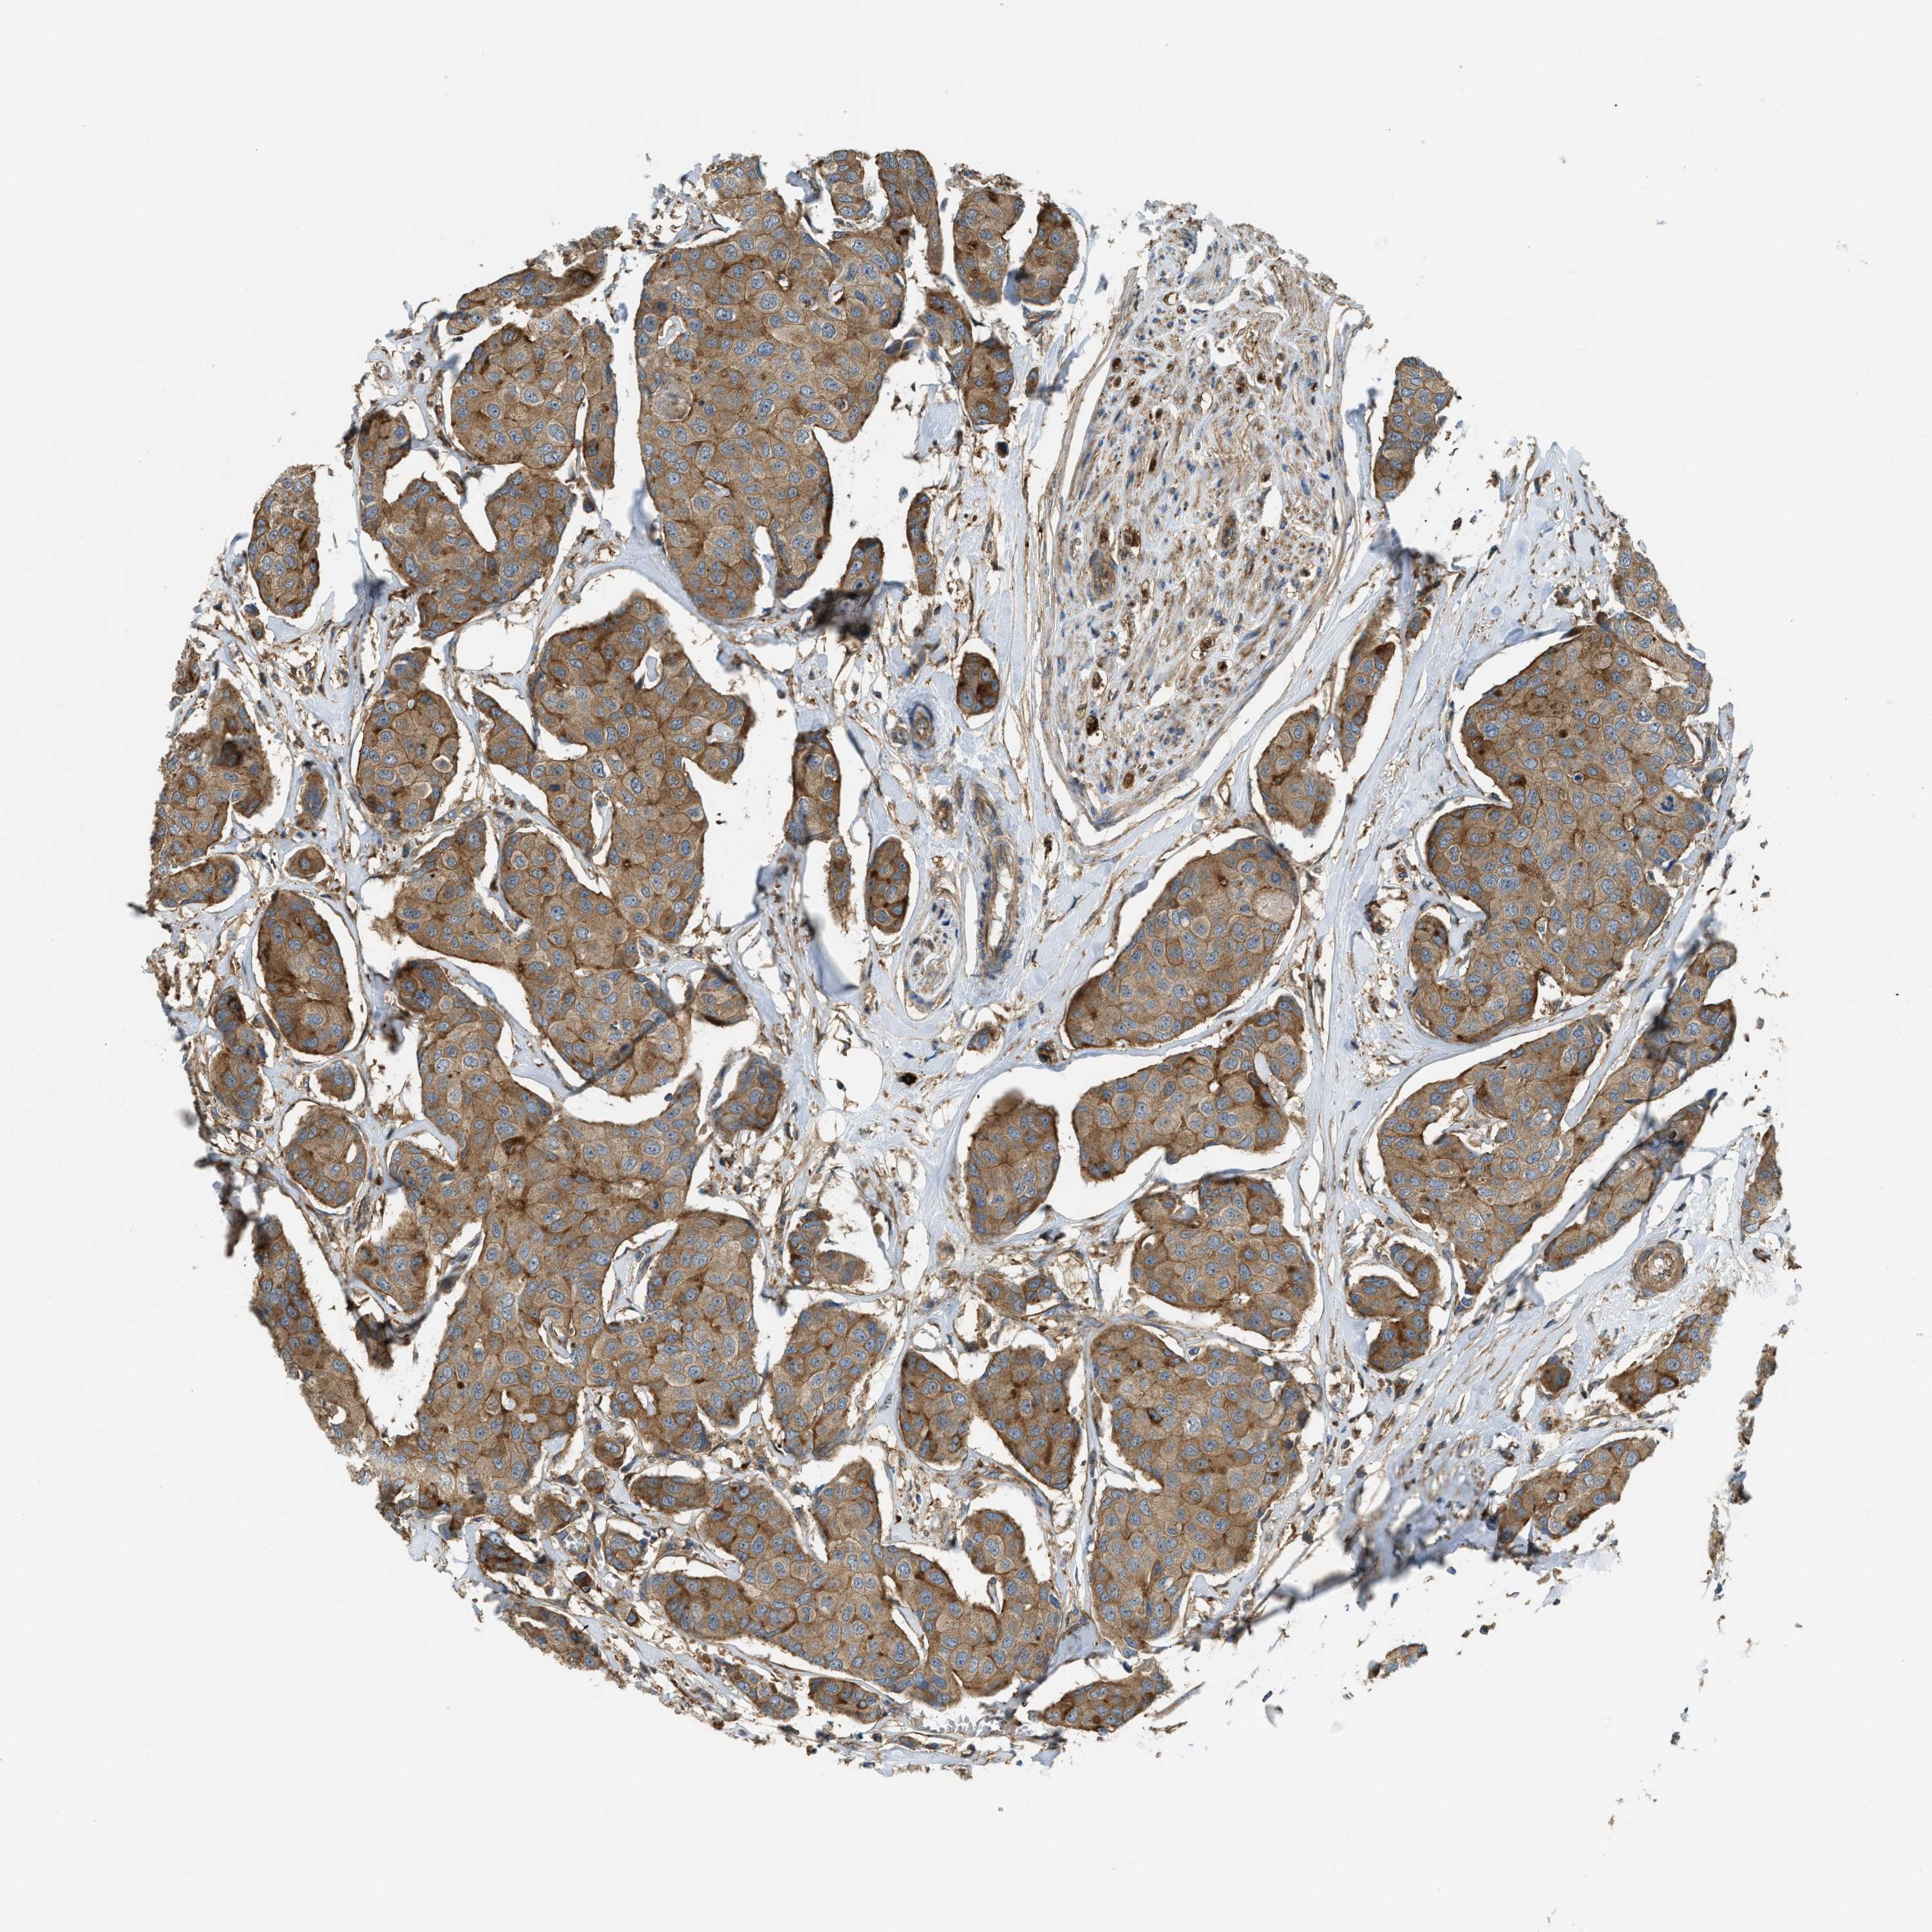

CANCER BREAST CANCER Show tissue menu

BRCA TCGA BRCA VALIDATION PROTEIN EXPRESSION